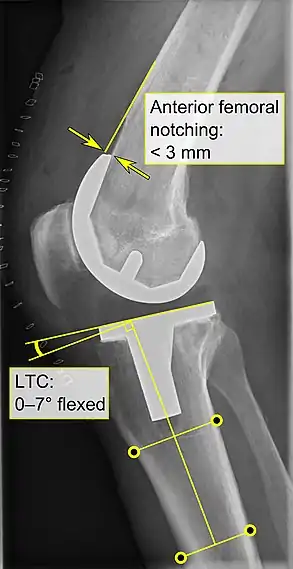

Knee replacement is routinely evaluated by X-ray, including the following measures:

- FFC: frontal femoral component angle. It is typically regarded as optimal when being 2–7° in valgus.[57]

- FTC: frontal tibial component angle, which is regarded as optimal when being at a right angle. A varus position of more than 3° has generally been found to increase the failure rate of the prosthesis.[57]

- Anterior femoral notching (the femoral component causing reduced thickness of the distal femur anteriorly), seems to cause an increased risk of fractures when exceeding about 3 mm.[58]

- LTC: lateral (or sagittal) tibial component angle, which is ideally positioned so that the tibia is 0–7° flexed compared to at a right angle with the tibial plate.[57]